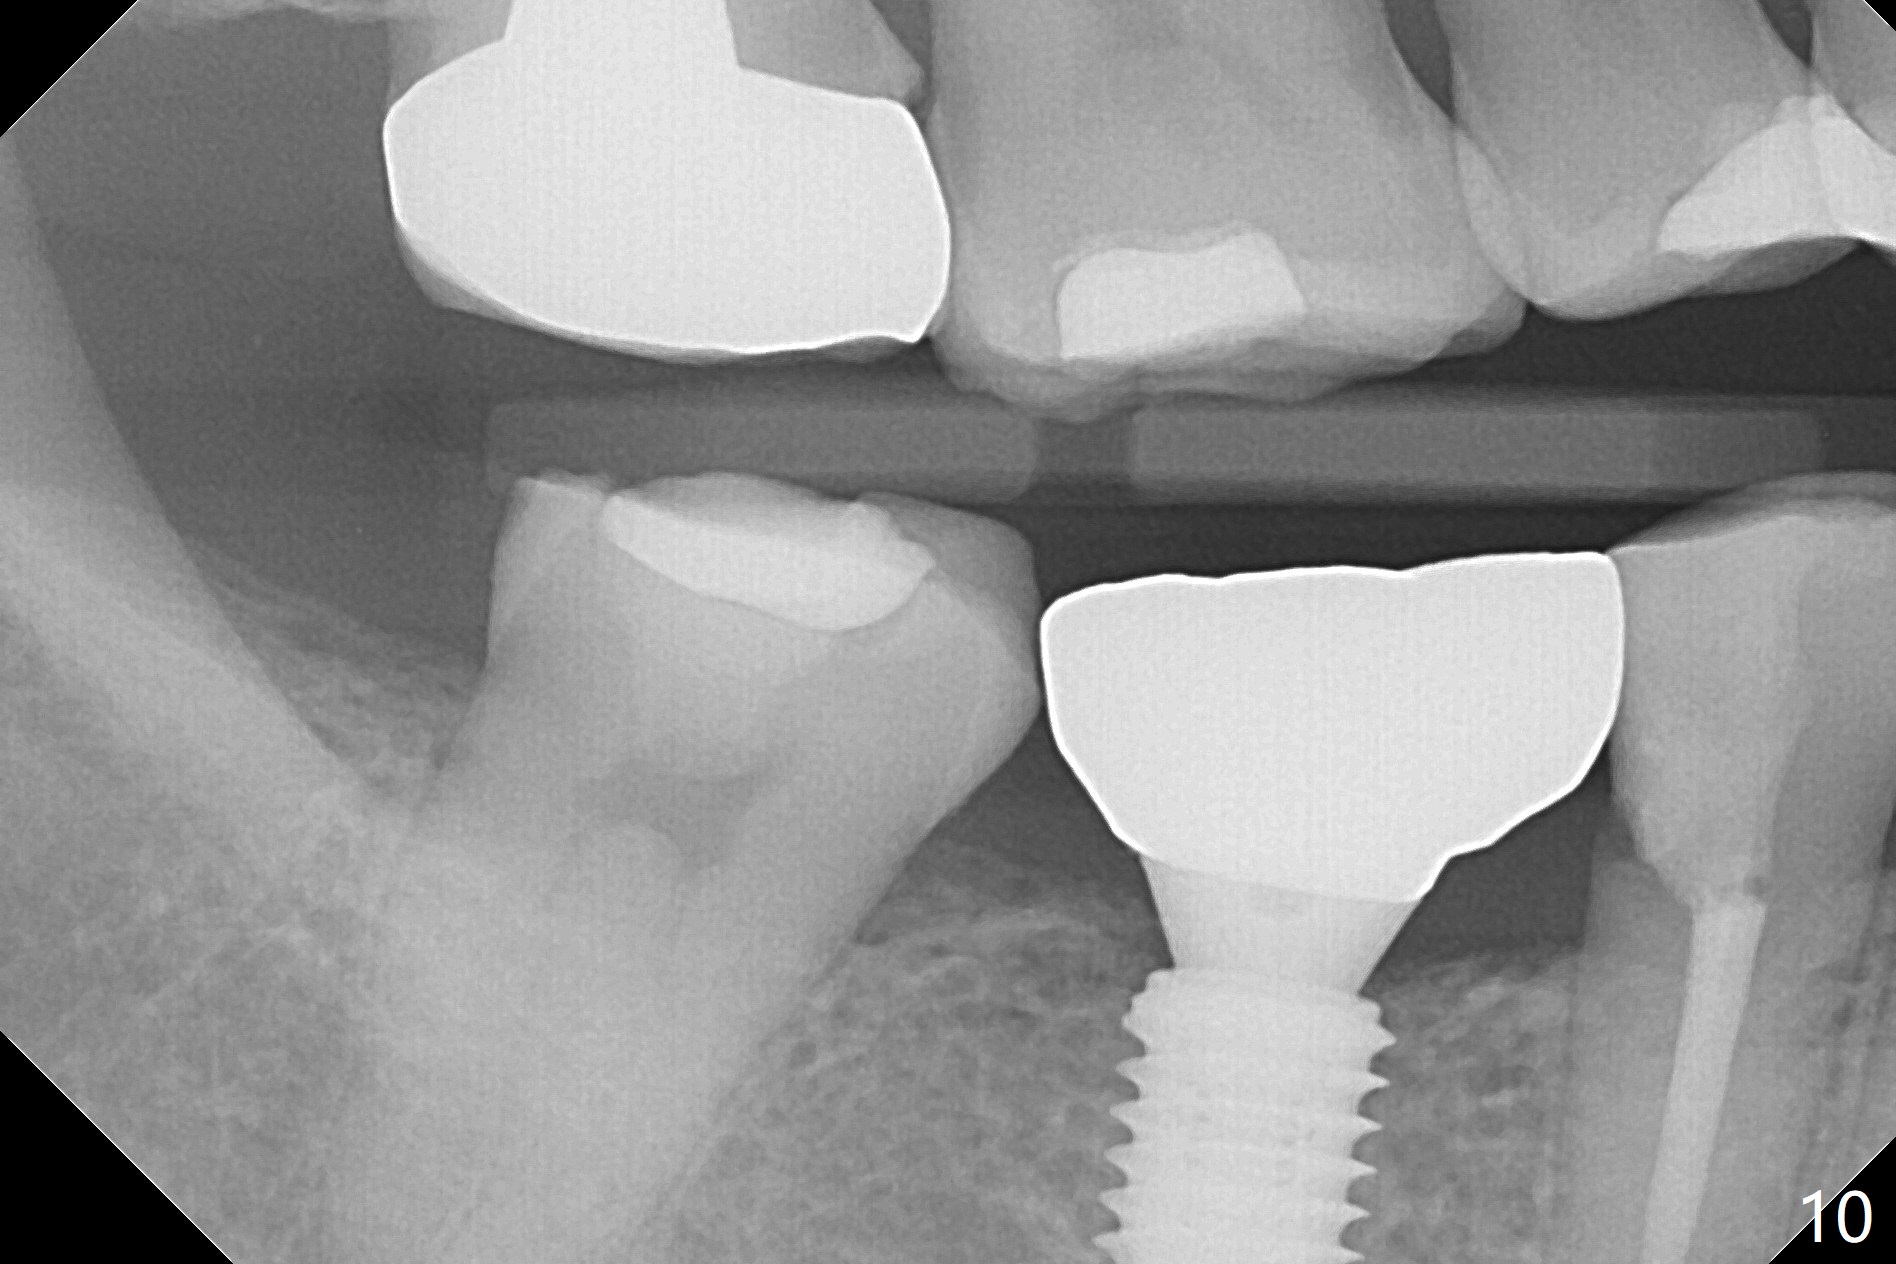

A 5x10 mm implant is placed at #30 with a surgical guide (Fig.1 *) in 10 minutes. The most amazing part of this surgery is that the guide allows you to place the implant at the precise level care-free (~ 1 mm subcrestal, Fig.2,3). Everything happens so quick that when a 5.5x3 mm healing abutment is placed (Fig.4), you are pleased to feel that the implant is stable (Fig.5). You could not ask for anymore. The fearful patient reports no postop pain. The implant is placed as planned (Fig.6, overlap image provided by the guide designer, Jennifer). The patient returns for impression nearly 2 months postop (Fig.7,8). It appears that the implant has osteointegrated without bone loss (Fig.7). The soft tissue is healthy around the just placed cementation abutment (Fig.8 (5.2x4(2) mm)). When the permanent crown is seated initially 2.5 months postop, the mesial contact is slightly tight and the occlusion is high. Bitewing shows the distal open margin (Fig.9 >). After mesial contact adjustment, the patient feels that the occlusion is better. With further occlusal adjustment, the crown is cemented without distal open margin (Fig.10). The patient returns to her home country for 3 months. The implant is doing well 3.5 months post cementation; impression is taken for #14 surgical guide.